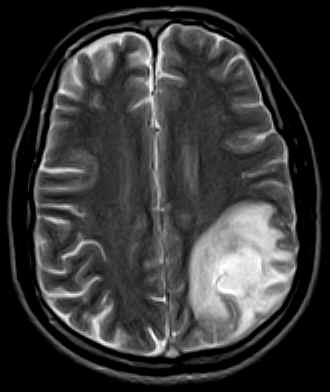

November 2005 - Venous Infarct

Diffuse hypointense areas on the T1W images which turn hyperintense on the Proton & T2W images are noted in the left parietal lobe. An area which is predominantly hypointense with a hyperintense rim on all sequences is noted in this lesion (subacute blood). The lumen of the superior sagittal sinus shows a hyperintense signal (no flow on the MRV-images not available) representative of a thrombus in this case.

On MRI:

·                     Diffuse distribution, not conforming to vascular territories (as seen with arterial infarcts).

·                     Hemorrhage may be present (20%).

·                     May find a lack of the normal flow void within a dural venous sinus (e.g. in the superior sagittal sinus).